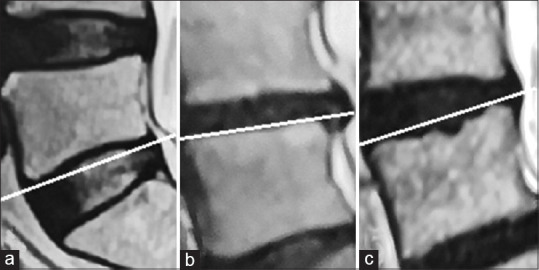

Materials and methods: A total of 116 patients were included in the study. Based on their MRI, we divided end plates into three types (concave, flat, and irregular), assigned intervertebral discs with Grade I-V given 1-5 points successively according to the Pfirrmann system, and determined whether there was Modic change of each end plate. The correlation between the morphology of the end plate and the degree of IDD was analyzed.

Results: There was an excellent interobserver agreement for each item we analyzed (interclass correlation coefficient >0.75). Concave end plate appeared most frequently (187, 53.7%) and was mainly distributed in L3/4 and L4/5, whereas irregular end plate was the least common type (54, 15.5%) and mainly concentrated in L5/S1. The IDD degree of the corresponding disc increased gradually from concave (3.27 ± 0.81) to irregular end plates (4.25 ± 0.79) (P < 0.05). Irregular end plates were more likely to have Modic changes than concave and flat end plates (P < 0.05).